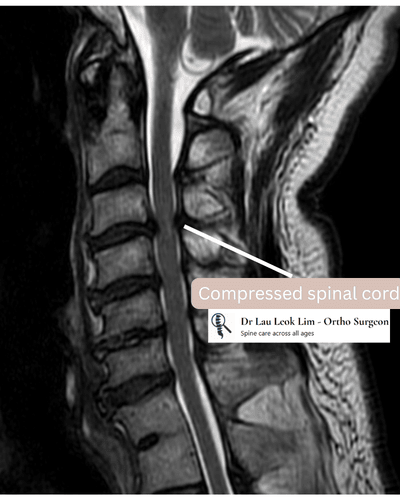

- MRI of the cervical spine to evaluate spinal cord compression

The Scoliosis & Spine Clinic (SG) provides clinical evaluation and management for cervical myelopathy—a progressive condition caused by spinal cord compression in the neck. Patients may experience hand dysfunction, walking imbalance, and upper limb weakness. This article explains how cervical myelopathy presents, what causes it, and how it is typically managed in Singapore.

What Causes Cervical Myelopathy?

- Degenerative cervical spinal stenosis

- Disc herniation or disc bulging compressing the spinal cord

- Bone spurs (osteophytes) narrowing the spinal canal

- OPLL causing progressive pressure on the spinal cord